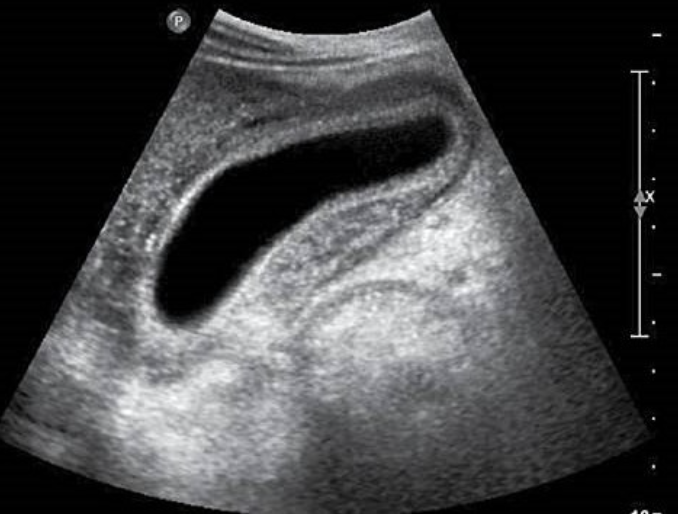

Hydronephrosis → dilation of renal collecting system from mechanical obstruction or functional dysfunction (calculi, mass, trauma, pregnancy)

clinical hx: prone to stones (stasis, pregnancy)

s/sx: if stone → renal colic, N&V, hematuria, frequency/urgency

2D US: grade 1 (mild) → pelviectasis, cortex preserved, grade 2 (mild to moderate) → expands into major calyces, cortex preserved, grade 3 (moderate) → expand all calyces, entire pelvis dilated, cortex preserved, grade 4 (severe) → cortical thinning, AKI to CKD, creatinine >1.2

color doppler: avascular

DDX: parapelvic cysts